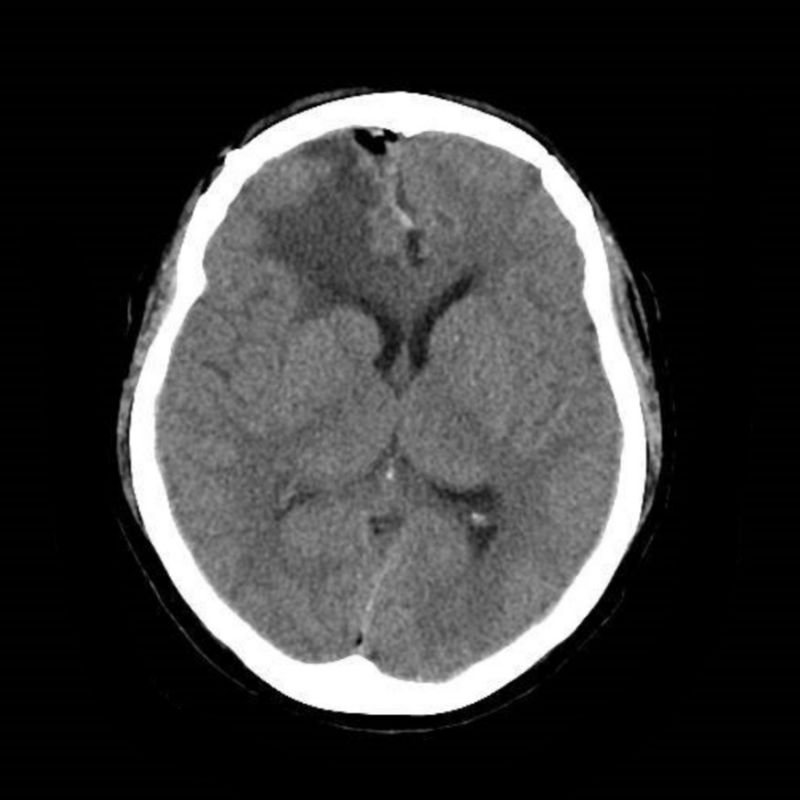

术后CT可见肿瘤切除完全,无出血等并发症。